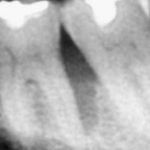

Inquadramento clinico e radiologico dei terzi molari in disodontiasi

Clinical and radiological classification of third impacted molars

L’estrazione dentale è una delle pratiche più comuni in...